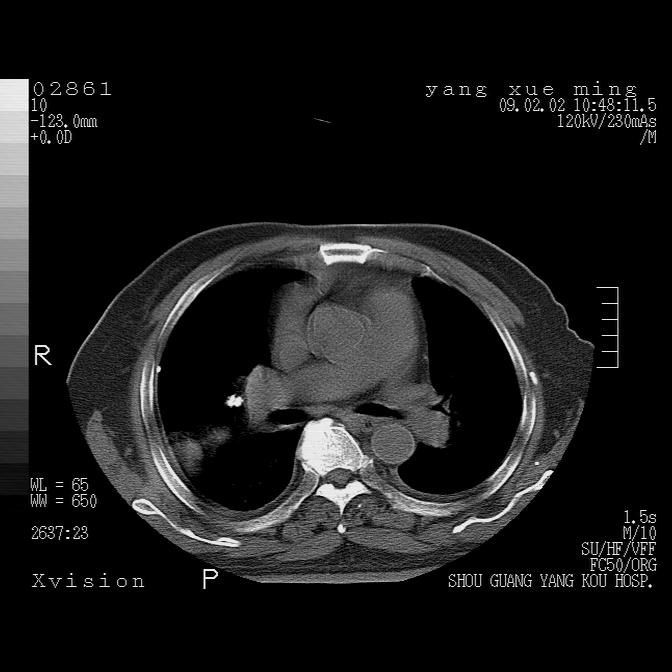

以下是引用zbp537在2009-2-3 19:08:00的发言:[br]我诊断为肺泡性肺水肿。[br]诊断依据:[br]1、心影普遍增大,肺血管增粗,并见絮状高密度影,肺门改变显著。[br]2、临床上表现胸闷咳嗽,无发烧,不是一个典型的肺部感染的病史。

以下是引用lkc8963在2009-2-3 20:11:00的发言:[br]1)右上肺陈旧病灶。2)右下肺团块及团片影,影像表现符合感染。3)左心增大,左冠脉钙化,符合冠心病。4)双侧肺门扩大,以左侧为著,肺动脉干略粗,左上肺局限性气肿,为谨慎起见,需除肿瘤,建议增强。

以下是引用lkc8963在2009-2-3 20:11:00的发言:[br]1)右上肺陈旧病灶.2)右下肺团块及团片影,影像表现符合感染.3)左心增大,左冠脉钙化,符合冠心病.4)双侧肺门扩大以左侧为著,肺动脉干略粗,左上肺局限性气肿,为谨慎起见,需除肿瘤,建议增强.